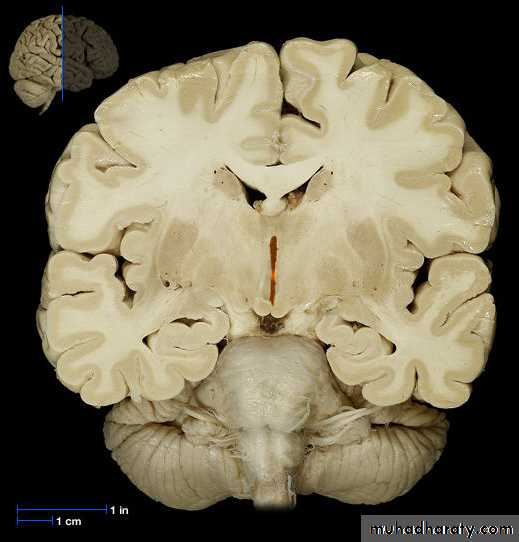

The Choroid Plexus

• The choroid plexus also helps to cleanse the• CSF by removing waste products and other

• unnecessary solutes

• Once produced CSF moves freely through the

• ventricles

Choroid Plexus

• Choroid plexushang from the

roof of each

ventricle

• These plexuses

• form CSF

• The plexuses are

• clusters of thin

• walled capillaries

• enclosed by a

• layer of

ependymal cells

3rd Ventricle

• It lies below the lateral ventricles.

• It is a cavity of the diencephalon. In the roof there is

choroid plexus, that produce CSF.

4th Ventricle

It is a cavity of the rhombencephalon• It has a roof and floor.

• The floor is formed by two parts, medullary & pontine part.

• The roof formed by cerebellum

• It has 3 foramina, one is median (foramen of Magendie) located posteriorly and two are lateral (foramina of Lushka)